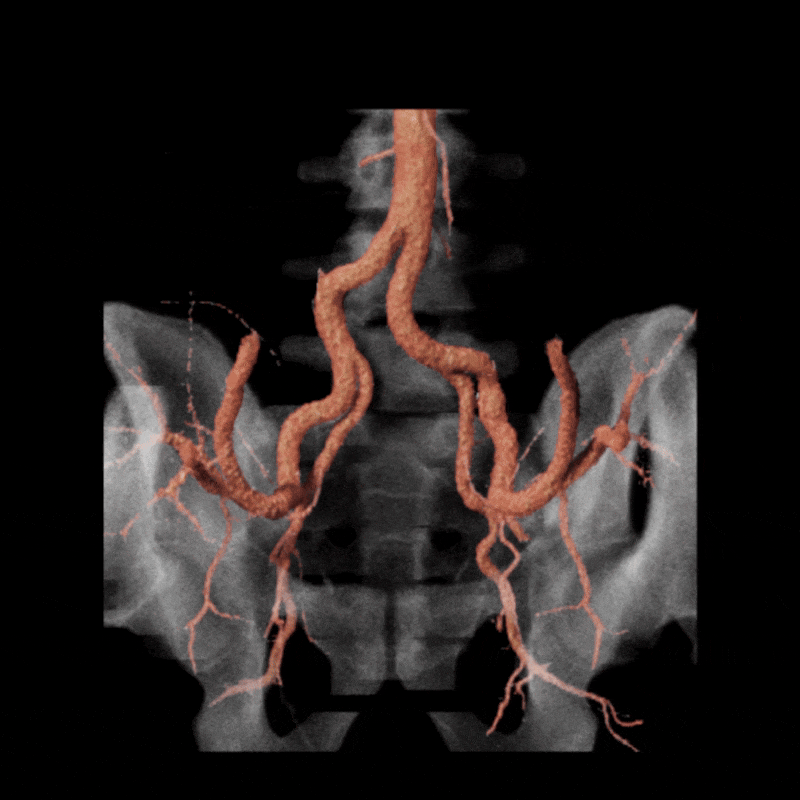

Figure A (Right): Rotational cinematic volume render of the iliac arteries (pink) and bone (transparent white) while in a stressed position.

A dynamic CTA was performed in both relaxed and stressed (flexed) positions to simulate the limb posture during activity. Changes in hip and pelvic motion can alter the course of the external iliac artery, and narrowing that affects blood flow may appear only when the limb is under tension. Imaging at rest alone may overlook these positional changes, so evaluating both postures helps determine whether the symptoms are related to dynamic vessel deformation rather than fixed structural disease. (Learn about a similar condition, popliteal entrapment, here).

Figure H: Rotational volume render of the iliac arteries in the stressed position.

When the patient moved into the stressed position, the right external iliac artery showed two areas of luminal narrowing (a temporary decrease in the size of the vessel’s opening). One narrowing was more proximal (closer to the vessel’s origin near the pelvis) at about ten to twenty percent, and the second was more distal (farther along the vessel toward the leg) at about thirty to forty percent. Both returned to a widely patent appearance (fully open) when the leg moved back to a relaxed position.

The left external iliac artery remained patent across positions, and the common iliac arteries were tortuous (naturally curving) without any fixed stenosis. This pattern aligns with external iliac endofibrosis, where motion causes the artery to change shape rather than a fixed obstruction, highlighting why positional imaging can reveal abnormalities that may not appear on routine resting studies.

Figure J (Right): Two areas of narrowing were identified in the right external iliac.